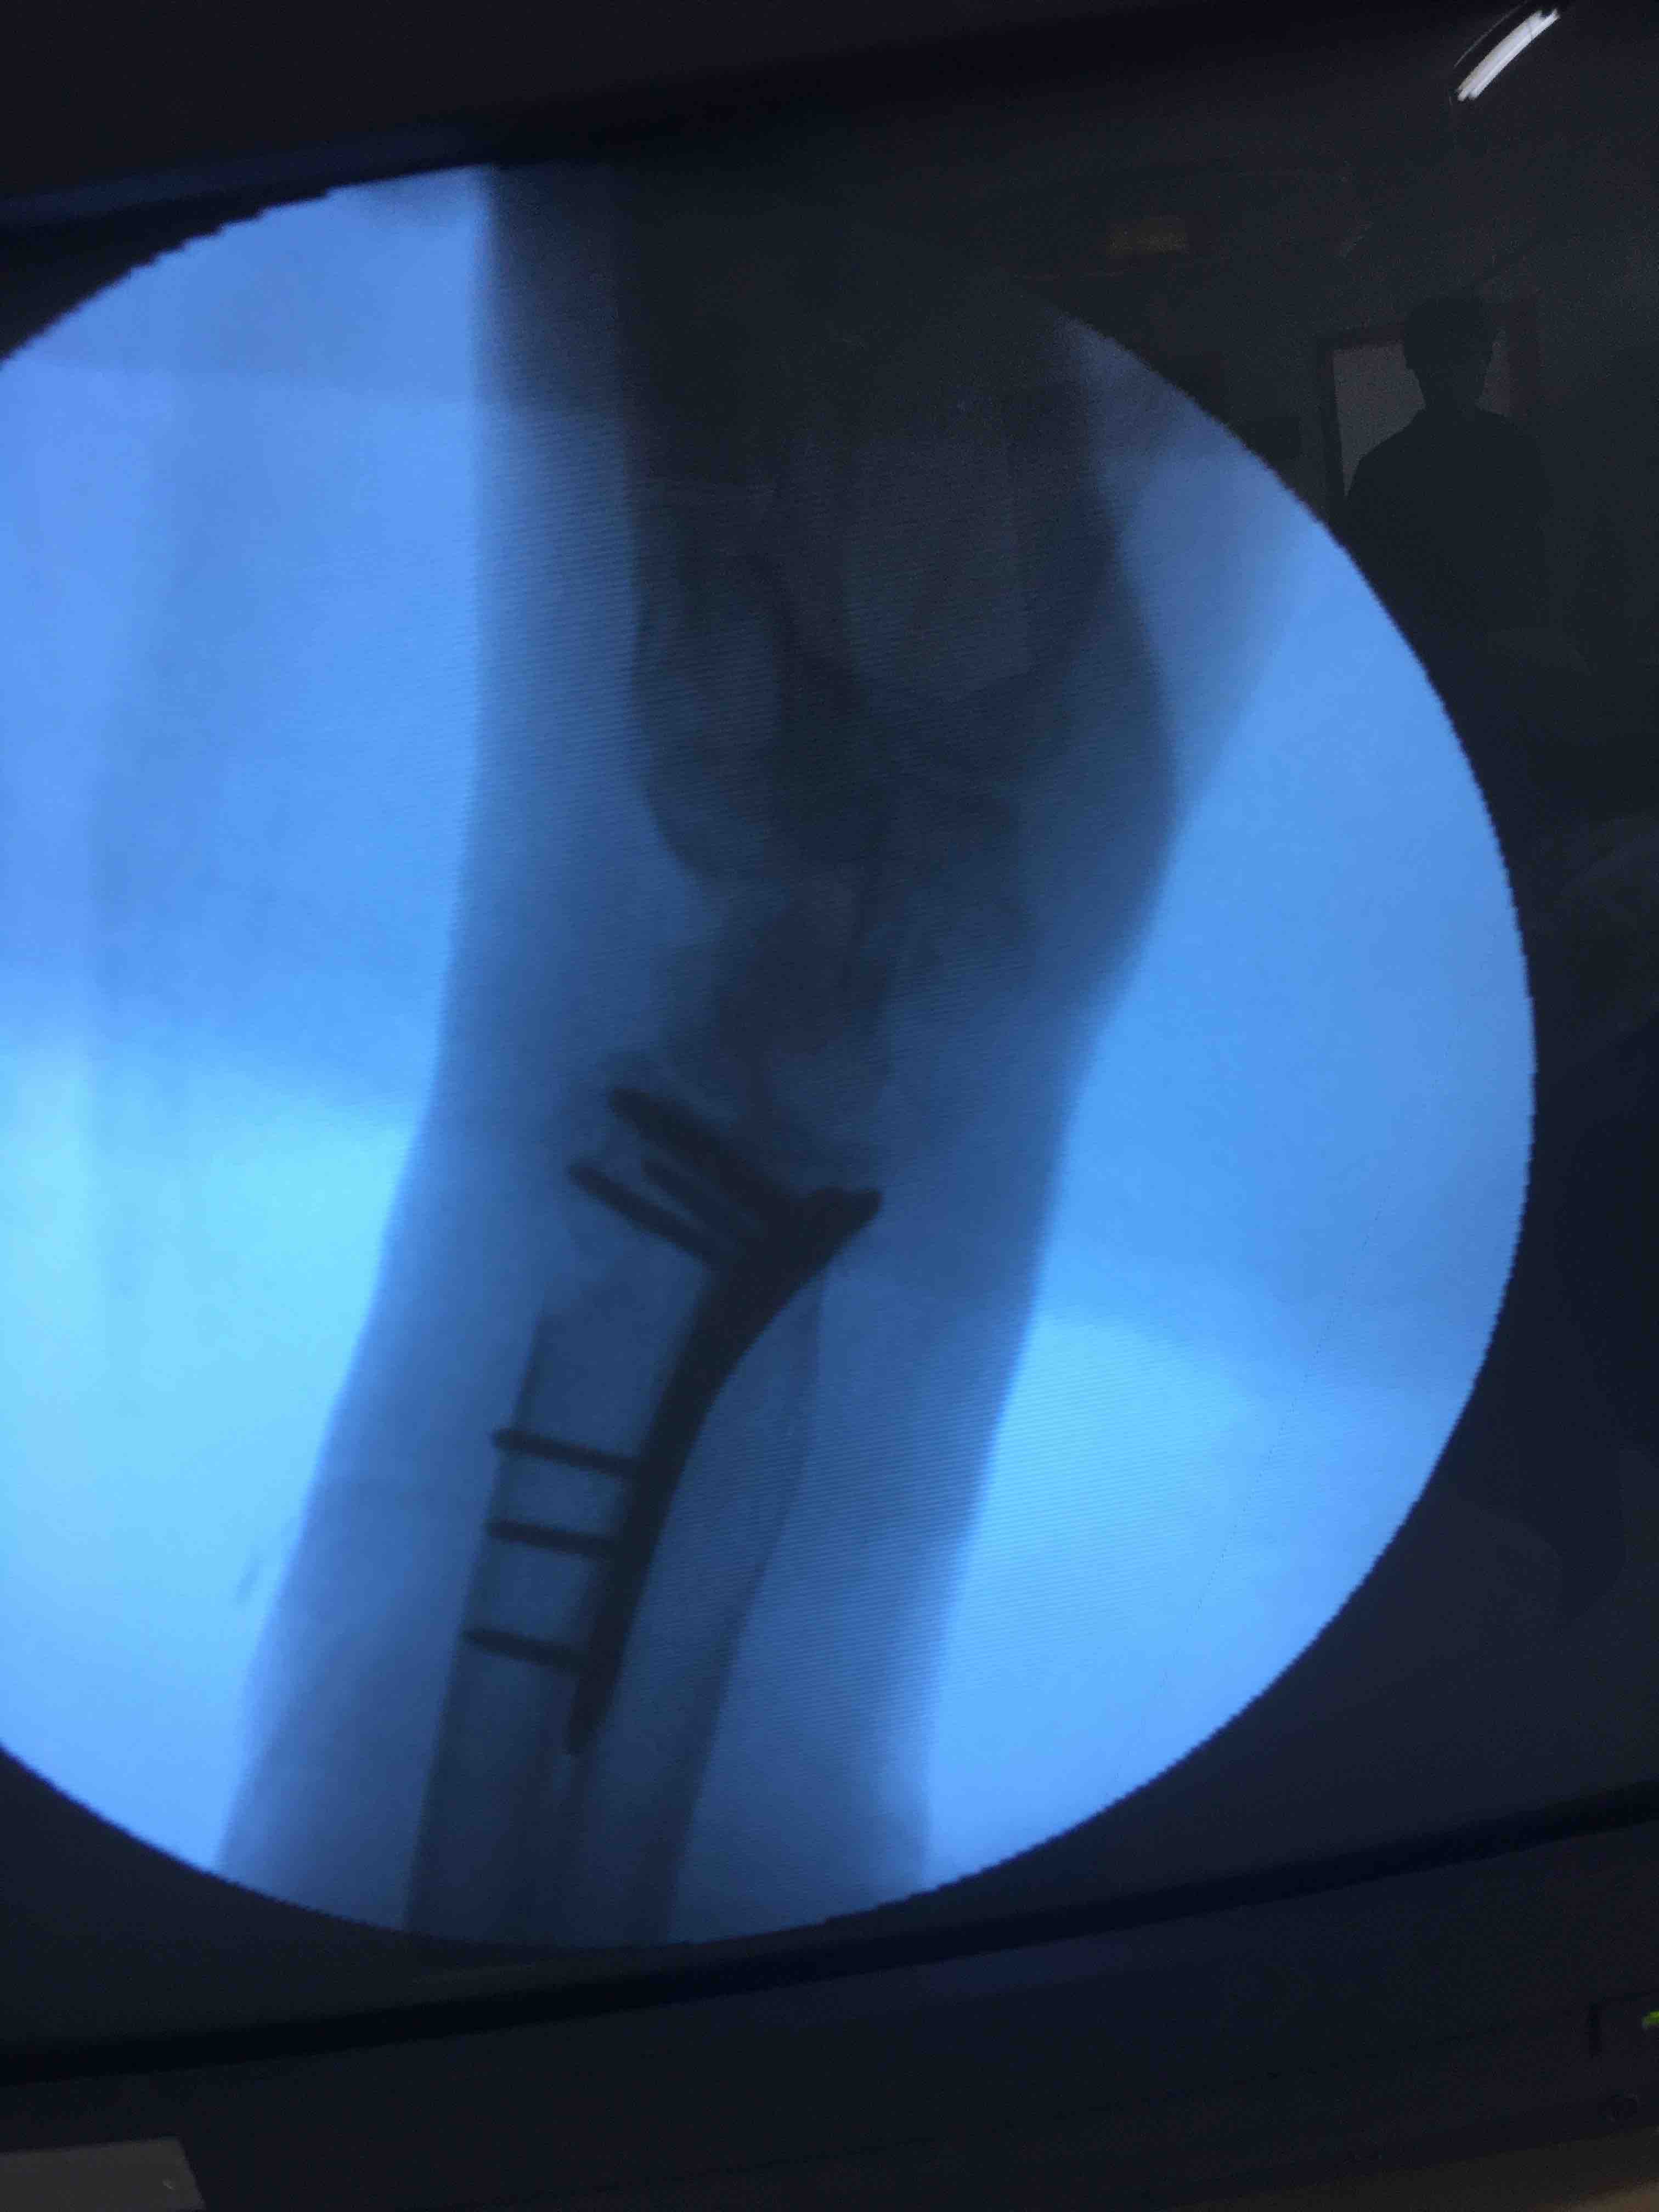

打开应用老年患者colles骨折(切复内固定术)

在臂丛麻醉下行切复内固定术,术后抗炎对症处理。